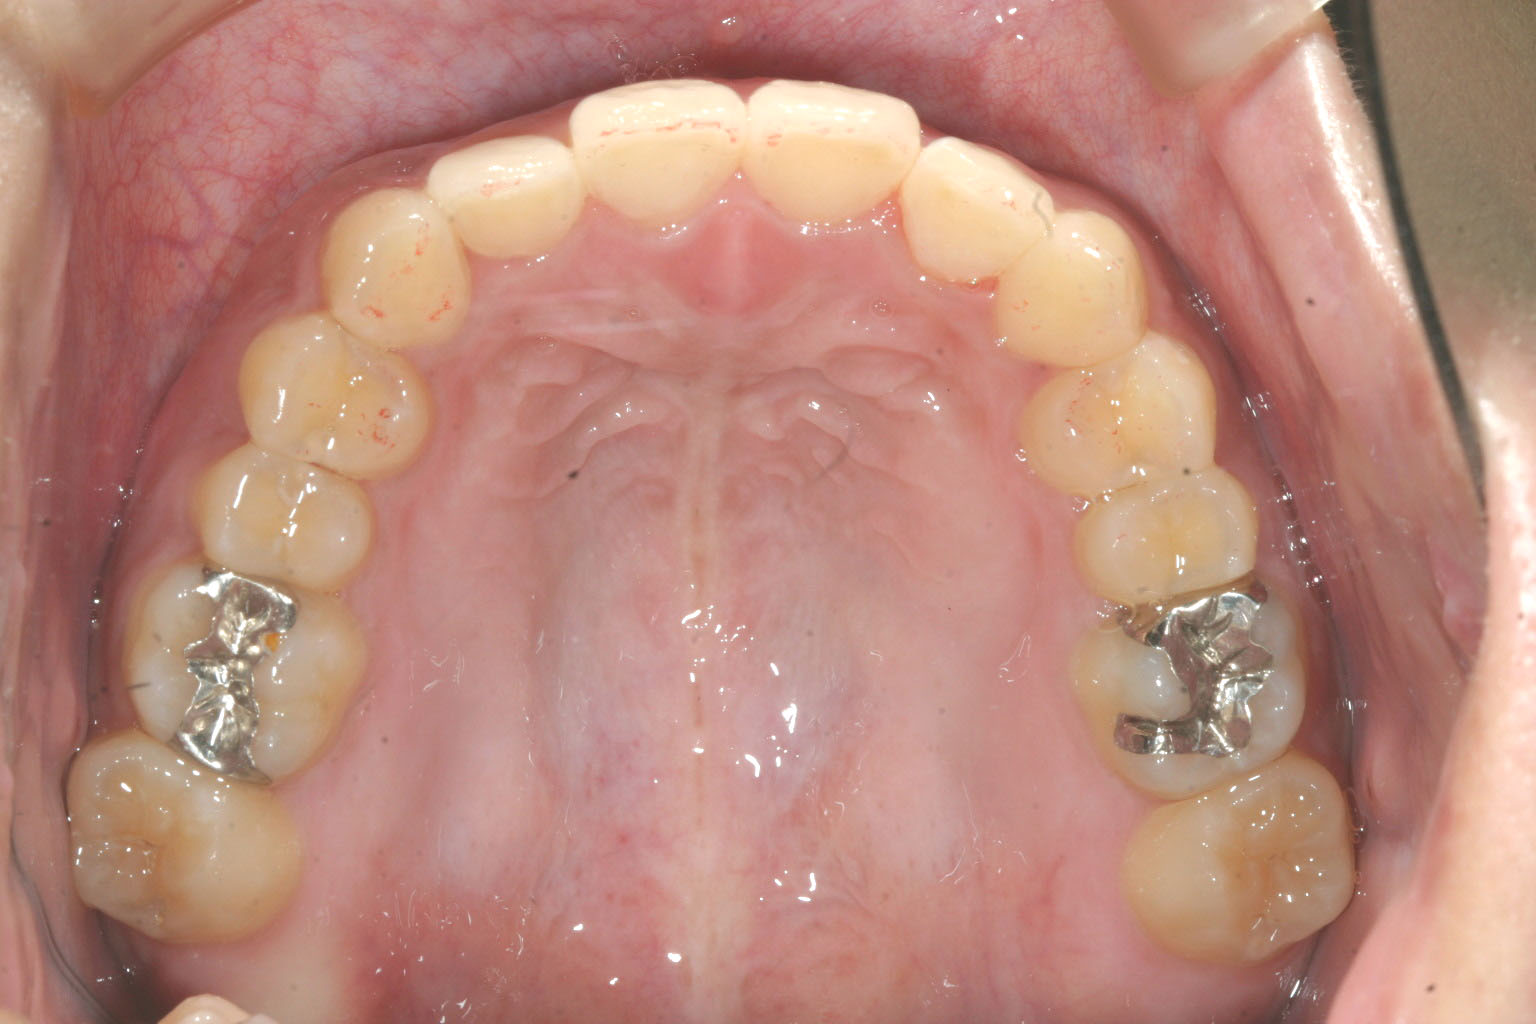

アーチを少し拡大し綺麗に並べてみました。

今回のケースは上下顎の前突と前歯のねじれ改善が大きな目的です。

全体的にアーチを拡大する事により叢生が取れ前突も改善し、更なる前突改善の為IPR(歯と歯の隙間を削る)を加えました。